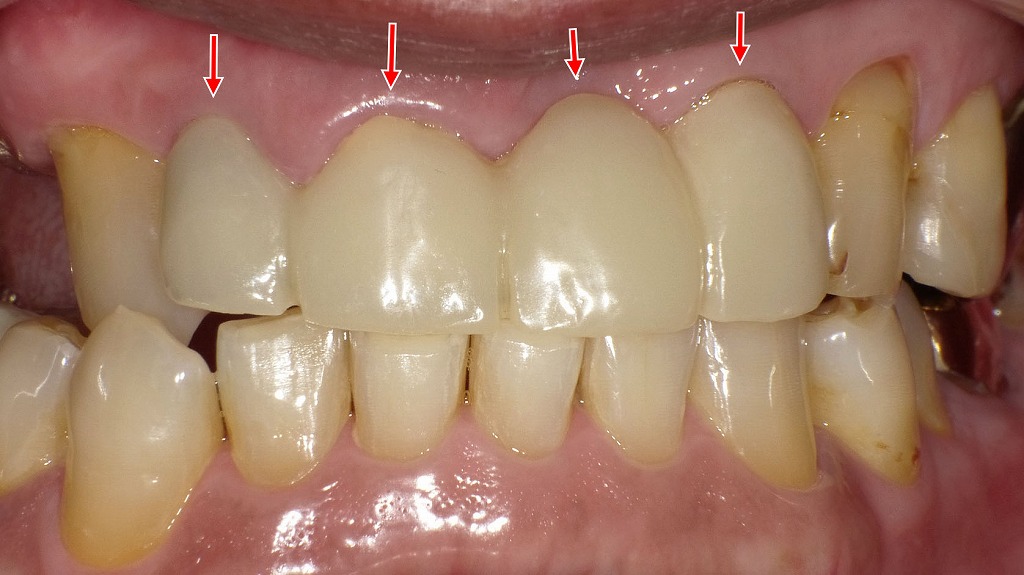

正面観

この画像は、上顎右側犬歯(3番)から左側犬歯(3番)までを連結したブリッジ形態の仮歯(テンポラリーブリッジ)の正面観です。

赤い矢印は、ブリッジの範囲(右上3番~左上3番)を示しています。

🦷 状況の説明

- 仮歯は、左右の犬歯(3番)を支台歯として連結され、中央の前歯部(1・2番)はポンティック(ダミー)構造になっています。

- 先に示された口蓋側の写真と同一症例であり、上顎前歯部の審美的仮歯段階です。

👁🗨 正面観からの所見

- 全体的な歯列形態・プロポーションは良好であり、左右対称性が保たれています。

- 歯軸もほぼ自然で、中央の切歯(中切歯・側切歯)部分の配列がスムーズに連続しています。

- 仮歯の長さ・幅比が自然で、スマイルラインに調和した形態に仕上がっています。

- 咬合平面(上の歯の並びのライン)も比較的安定しており、審美的バランスが良い状態です。

⚠️ 補足(内部構造的留意点)

- 支台歯は左右の犬歯のみのため、中央部のブリッジスパン(距離)が長く、たわみやすい構造です。

- したがって、最終補綴時には:

- 材質選択(ジルコニアなどの高強度素材)

- フレーム設計(十分な連結部厚み)

- 咬合調整(過大な咬合力回避)

が重要となります。

💡 総合評価

- 形態的には非常に良好で、最終補綴に向けた審美的・機能的確認段階として適切です。

- 今後は、歯頚部の適合改善(前画像の指摘)と、歯肉ラインの調整を行うことで、より自然で清掃性の高い最終形態が期待できます。